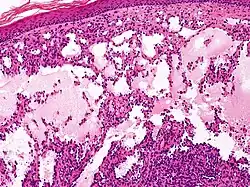

Proliferating lymphangioma, H&E stain. Sometimes endothelial cells begin to divide excessively.

In 1976, Whimster studied the pathogenesis of lymphangioma circumscriptum, finding lymphatic cisterns in the deep subcutaneous plane are separated from the normal network of lymph vessels. They communicate with the superficial lymph vesicles through vertical, dilated lymph channels. Whimster theorized the cisterns might come from a primitive lymph sac that failed to connect with the rest of the lymphatic system during embryonic development.

A thick coat of muscle fibers that cause rhythmic contractions line the sequestered primitive sacs. Rhythmic contractions increase the intramural pressure, causing dilated channels to come from the walls of the cisterns toward the skin. He suggested that the vesicles seen in lymphangioma circumscriptum are outpouchings of these dilated projecting vessels. Lymphatic and radiographic studies support Whimsters observations. Such studies reveal that big cisterns extend deeply into the skin and beyond the clinical lesions. Lymphangiomas that are deep in the dermis show no evidence of communication with the regular lymphatics. The cause for the failure of lymph sacs to connect with the lymphatic system is not known.[7]

Microscopically, the vesicles in lymphangioma circumscriptum are greatly dilated lymph channels that cause the papillary dermis to expand. They may be associated with acanthosis and hyperkeratosis. There are many channels in the upper dermis which often extend to the subcutis (the deeper layer of the dermis, containing mostly fat and connective tissue). The deeper vessels have large calibers with thick walls which contain smooth muscle. The lumen is filled with lymphatic fluid, but often contains red blood cells, lymphocytes, macrophages, and neutrophils. The channels are lined with flat endothelial cells. The interstitium has many lymphoid cells and shows evidence of fibroplasia (the formation of fibrous tissue). Nodules (A small mass of tissue or aggregation of cells) in cavernous lymphangioma are large, irregular channels in the reticular dermis and subcutaneous tissue that are lined by a single layer of endothelial cells. Also an incomplete layer of smooth muscle also lines the walls of these channels. The stroma consists of loose connective tissue with a lot of inflammatory cells. These tumors usually penetrate muscle. Cystic hygroma is indistinguishable from cavernous lymphangiomas on histology.[7]